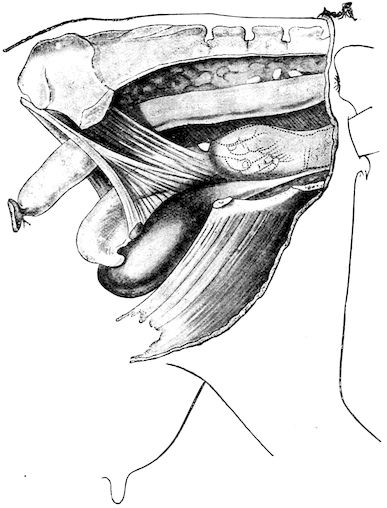

2. The second phase is characterised by more precise signs, which become almost pathognomonic. Difficulty in rising is added to the already existing tendency to remain lying, and to the interference with movement.

When lying down the patient no longer responds to the trifling stimulus, which a healthy animal needs to cause it to rise. It remains languid and apparently lazy, though in reality it experiences pain and difficulty on attempting to get up. The least muscular effort when lying down often causes it to moan, as do efforts to change its position or to walk. Even when standing still, it may appear to be in pain, and patients often assume a position similar to that of a horse suffering from laminitis.

At the end of this second phase, swellings appear, due to synovitis or arthritis of the extremities, synovitis of the sesamoid or navicular sheaths or to inter-phalangeal arthritis or arthritis of the fetlock joint. Weakness becomes marked, and the appetite is very irregular.

10Secretion of milk diminishes or ceases and abortion is not uncommon.

3. The third phase is characterised by fractures, and it is this peculiarity of the disease which has procured for it the names of fragilitas ossium, and osteoclastia. These fractures may affect any portion of the skeleton. Animals so suffering sometimes break a leg whilst trotting or the pelvis in simply jumping over a ditch; a collision with a fixed object like the jamb of the stable door, or a fall on the ground, may result in the fracture of one or several ribs.

Fig. 3.—Pig suffering from osseous cachexia (fourth stage).

Such shocks would be of no importance to a healthy animal, but to one suffering from osseous cachexia, any violence, or even the slightest muscular effort may be followed by fracture of the gravest character, involving even the vertebral column. In cows the pelvis, femur, and tibia are most frequently injured.

In horses, particularly in riding horses, fractures are commonest in the region of the forearm, cannon bone, and anterior phalanges. So extremely fragile are the bones at this stage that the horse represented herewith broke twelve ribs at one time by simply falling on its side. It is interesting to note that such fractures are never accompanied by any extensive bleeding. They have little tendency to repair, no real callus formation occurs, and on post-mortem examination one often finds the ends unconnected by temporary callus, worn, and rounded by reciprocal friction.

At this stage but under other circumstances, the animals show great reluctance to rise, remaining down for twelve to twenty-four hours without shifting their position. If forced to get up, they stand as though fixed in one position, the respiration and circulation become rapid, and they soon grow tired and fall.